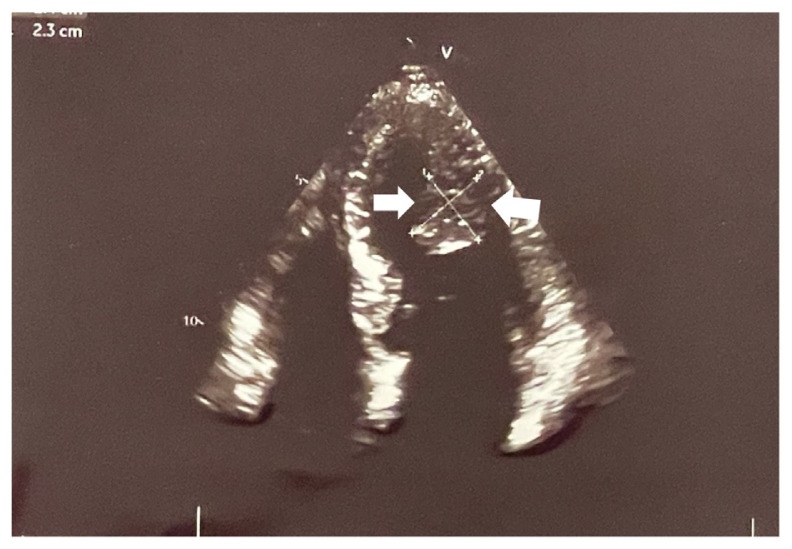

Case presentation: We present a case of a 46-year-old woman with positional vertigo and exertional dyspnea. Transthoracic echocardiography revealed a mobile oval-shaped mass in the left ventricle. Cardiac magnetic resonance imaging suggested a large papillary fibroelastoma. The tumor was successfully resected, and histopathological examination confirmed the diagnosis.